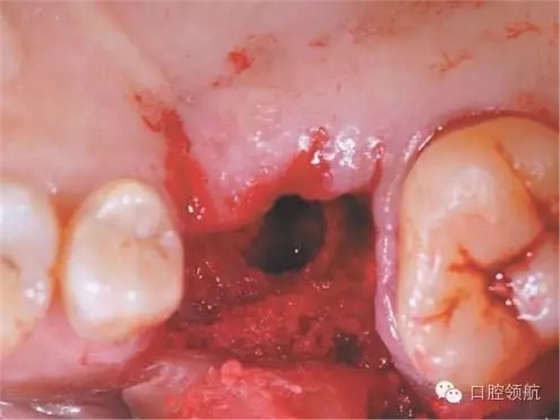

圖2 拔牙后4周,牙齦上皮完全覆蓋拔牙窩。

完全去除拔牙窩內(nèi)的肉芽組織,造成上頜竇底的青枝骨折(圖4),植入骨替代材料行上頜竇底提升術(shù)。

圖4 確認(rèn)上頜竇黏膜增厚消失,而且OMC的換氣和排泄功能已改善后,實施經(jīng)牙槽嵴頂入路的上頜竇底提升術(shù)。按照常規(guī),造成上頜竇底的青枝骨折,提升上頜竇底。